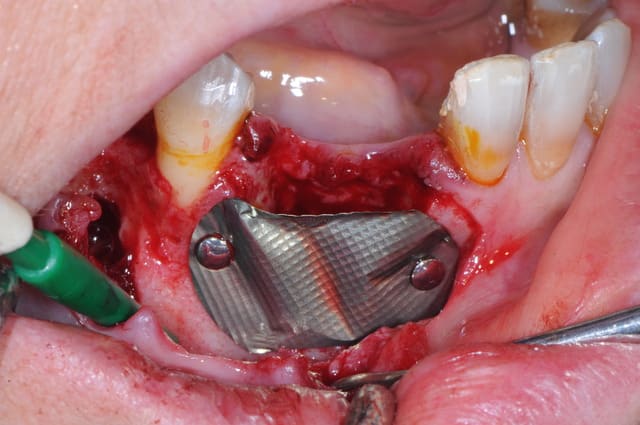

les photos de l'intervention...

photo 1-2-3 ouverture et extraction de 42 puis par la suite de 43 car l'étendu de l'infection était trop importante

09/07/2014 à 14h40

1: petit bout d'os entre l'incisive et la canine

2: le défaut osseux

3 début de la dissection du nerf

4 je remonte du trou mentonier en direction de l'origine du kyste

5-8 une partie du kyste se trouvait inta osseux et extra osseux sur la table externe mandibulaire

le plus dure c'est de faire la différence entre la membrane du kyste et le nerf lui même

maintenant, la phase reconstruction de la zone antérieure.

1 défaut osseux (y a plus grand chose!)

2 essayage de la membrane titane

3 stabilisation de la membrane

4 comblement osseux

reste plus qu'à attendre...